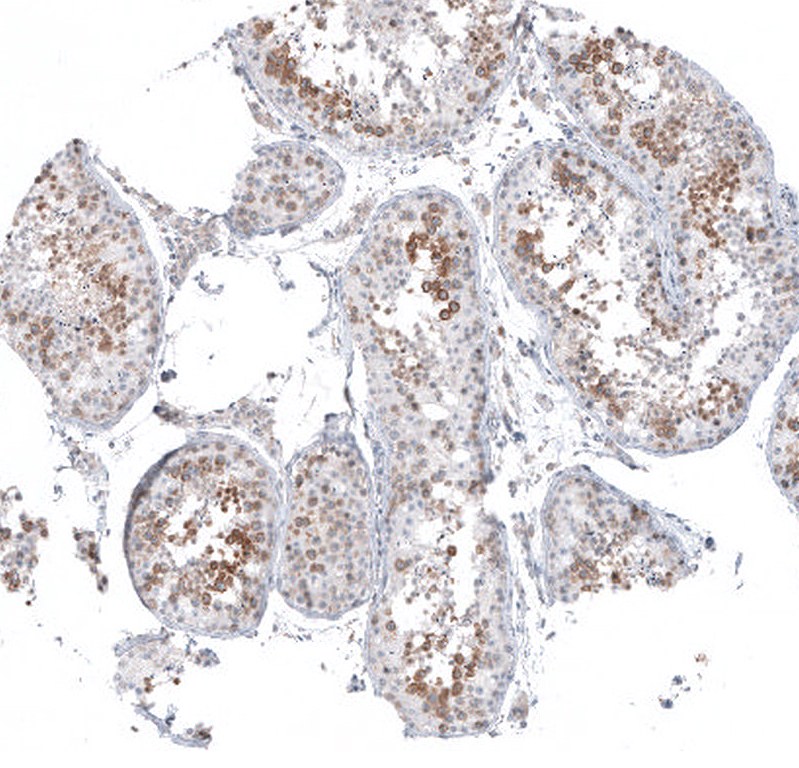

Immunohistochemical staining of human testis shows moderate to strong cytoplasmic positivity in cells in seminiferous ducts.